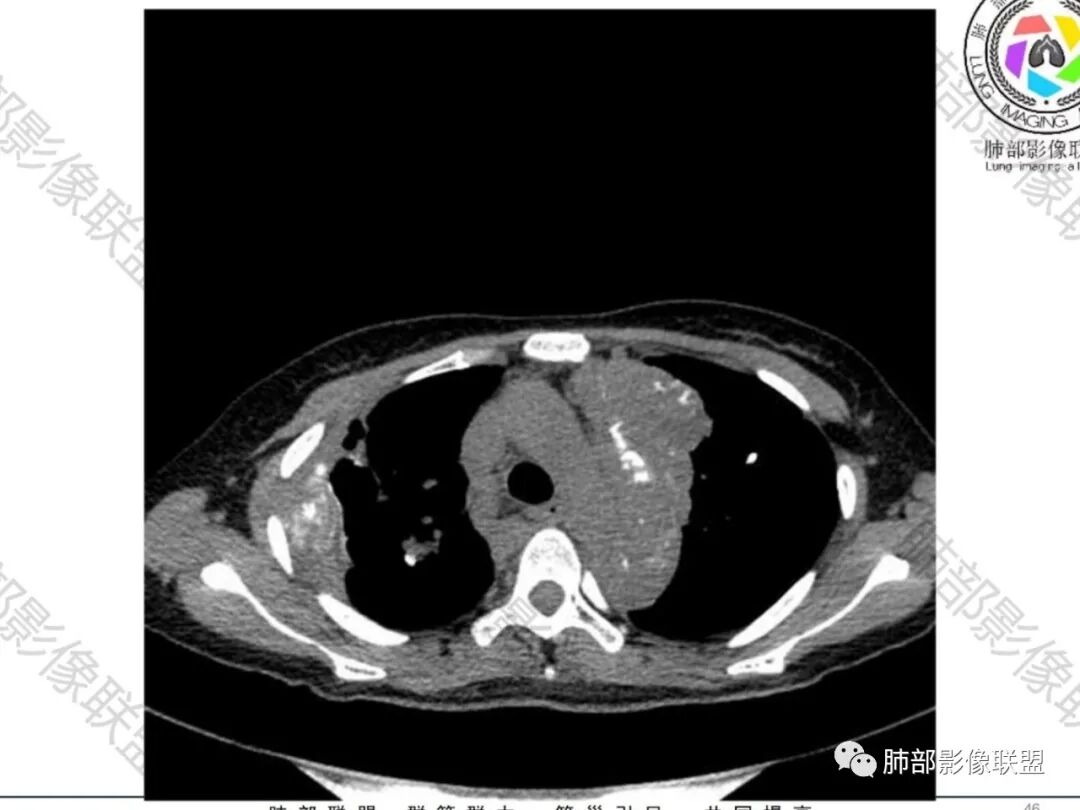

尘缘:青年女性,痰中带血,胸痛2月,无发热盗汗,实验室检查,有贫血,总蛋白降低,血沉情况未知,肿标基本正常。影像表现:双上肺小叶间隔增厚,双侧胸膜广泛不规则增厚,胸膜下多发肿块伴不规则钙化,右侧肋骨破坏。纵隔淋巴结肿大不明显,双肺门淋巴结肿大,部分融合,分析思路:一、感染性病变,1、结核,青年女性,胸膜增厚,多发肿块伴钙化,有咳嗽胸痛,痰中带血,要考虑,但无结核中毒症状,病史仅两月却钙化太明显,肺内没有明显树芽征,存疑,2、其他感染,无炎性指标支持,白细胞不高,可能性小。二、非感染性病变,1、尘肺,胸膜增厚,钙化,胸膜下钙化性肿块,要考虑,但肺内无粉尘结节,无职业史,可能小。2、转移性钙化,无肾脏病史,无血清钙磷代谢异常指标支持,肺内间质无钙沉积改变,基本排除。三、肿瘤性病变,1、肺癌伴转移,双上肺有小叶间隔增厚,双肺门有淋巴结肿大,要考虑,但青年女性,病史两月,钙化太多太广泛,肿标基本正常,可能性小。2、骨肉瘤转移。15-30岁青年人,是骨肉瘤高发年龄,肺内多发成骨样钙化转移灶,双上肺小叶间隔增厚符合癌淋样表现,右侧肋骨破坏,要高度怀疑,需要详细询问病史及手术史。3、软骨来源肿瘤伴肺内转移,右侧肋骨虽有破坏,但无明显软骨样破坏及钙化。可能小。4、其他肿瘤伴转移,青年女性,其他恶性肿瘤能广泛发生钙化性转移的可能性小。综上所述:骨肉瘤伴右侧肋骨及胸膜转移,胸膜下转移,肺内癌淋可能最大,结核不完全除外,下一步需要,仔细询问病史,如果有骨肉瘤史,则基本确诊,如果没有,需要进一步问询呼吸系统症状,病程,以前的影像对照,了解肾脏情况,查血清钙磷指标。

上叶内多个结块,边缘有膨隆,内有钙化灶

钙化灶密度较高,环形/结节状

胸膜及附近肺内见多发结节/斑块

胸膜结块,有侵袭性

但是都有多发钙化

肋骨伴随有溶骨性/成骨性骨质破坏,常规还是要警惕恶性